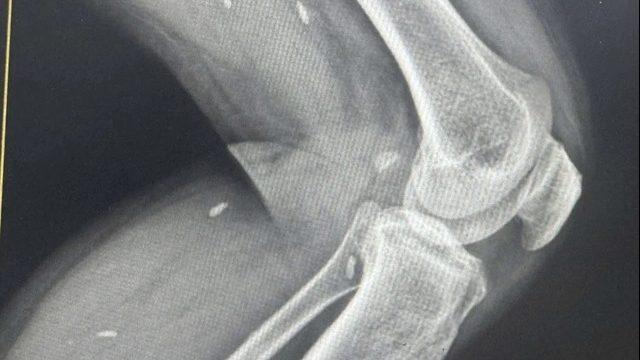

ThS.BS Trần Hữu Thắng – Trưởng khoa Cấp cứu, Bệnh viện Tai Mũi Họng Trung ương, bác sĩ trực tiếp điều trị cho bệnh nhân cho biết, anh H. bị tổn thương nặng, vỡ phức tạp vùng mặt. Hình ảnh chụp cắt lớp vi tính cho thấy bệnh nhân bị chấn thương tầng giữa sọ mặt, gãy ngành lên xương hàm trên, vỡ xoang hàm, vỡ sàn ổ mắt làm tụt kẹt nhãn cầu vào trong xoang hàm bên trái. Rất may, não anh không bị tổn thương.

Tuy nhiên, bệnh nhân có nguy cơ mất thị lực do nhãn cầu bị tụt kẹt, di lệch khớp cắn do gãy ngành lên xương hàm trên, biến chứng có thể gây tàn phế nghiêm trọng cho bệnh nhân.

Các bác sĩ đã phẫu thuật nắn chỉnh xương, lấy bỏ mảnh xương vụn, dùng nẹp vít kết hợp xương, lót lưới titan sàn ổ mắt để đưa nhãn cầu về đúng vị trí giải phẫu, kết hợp với mổ nội soi dẫn lưu xoang hàm bên trái, khâu thẩm mỹ phục hồi da vùng mặt.

Theo bác sĩ Thắng, quá trình phẫu thuật đòi hỏi sự khéo léo, tỉ mỉ, chính xác để sắp xếp lại đúng vị trí giải phẫu xương gãy, đảm bảo chức năng của mắt, mũi và khớp cắn. Khi nâng nhãn cầu lên vị trí hốc mắt cần tránh làm tổn thương các thành phần như cơ vận nhãn, bao ổ mắt, giác mạc,… để không ảnh hưởng đến thị lực người bệnh.